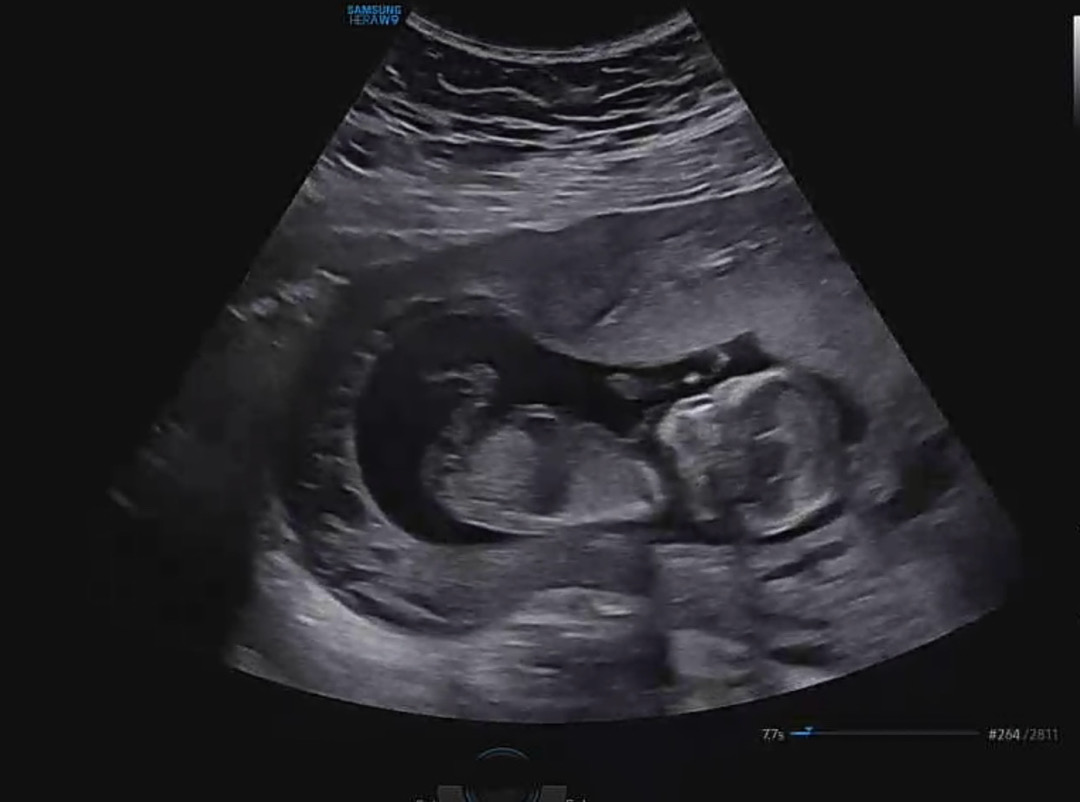

13주 각도법 봐주세용♥️

각도법으로 봤을때 성별이 뭘로보일까용?? ㅠㅠㅎ

조심스래 아들에 한표요! (갠적 느낌일 뿐입니다;;)